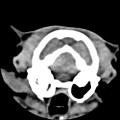

CT - lebka